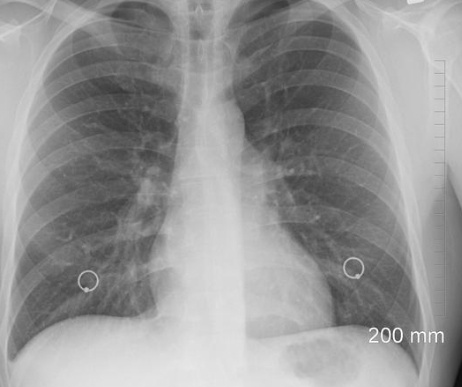

오른쪽 가슴 통증 원인 질환 2. 폐 질환

폐암, 흉막염, 자연기흉 등이 원인이 되어 나타날 수도 있습니다. 흡연자, 불규칙한 생활을 하거나 하는 사람은 아무래도 폐가 약할 수 있습니다. 그리고 10~30대의 마른 체형의 남성에게서는 자연기흉이 나타날 수도 있습니다.

폐 질환으로 인해 오른쪽 가슴 통증 나타나는 경우는 욱신거리는 통증과 가래를 동반한 기침 그리고 숨쉬기 괴롭고 힘든 증상이 나타납니다. 이런 경우는 바로 내과나 호흡기내과 등에서 진찰과 치료를 받아야 합니다.